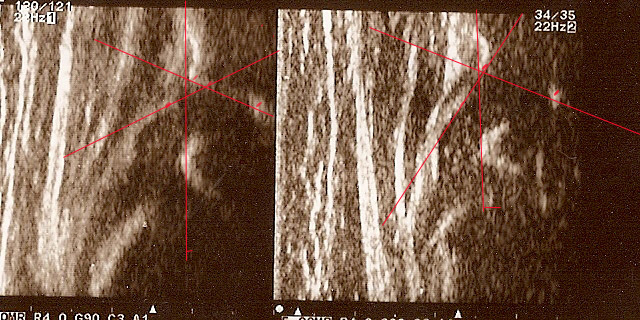

typIIa 6tyg.ż. dach kostny wystarczajacy;brzeg kostny kanciasty(mimo dysplastycznej panewki) pierwsza część dachu dobra ,

druga głębsza stroma(trzeba na to uważać) ;dach chrzestny pokrywa

górne zdjęcia strzałki pokazują obrabek(czerwona):brzeg kostny (żółta);gałąż dolna(niebieska) ,

prawidłowy przebieg linii dachu kostnego(niebieska) stycznie do echa gałęzie dolnej i echa brzegu kostnego ;

linii dachu chrzęstnego (czerwona) stycznie do brzegu kostnego i przez środek geometryczny obrąbka i

linii podstawnej ( żółtarównolegle do sylwetki kości biodrowej po zewnetrznej stronie prze punkt gdzie ochrzęstne przechodzi w okostna i styka sie z echem kości

dolny staw prawidłowy Typ I dach kostny dobry;brzeg kostny tępy ;dach chrzestny pokrywa

dolne zdjęcia strzałki pokazują obrabek(czerwona):brzeg kostny (żółta);gałąż dolna(niebieska) ,

linii podstawnej ( żółta